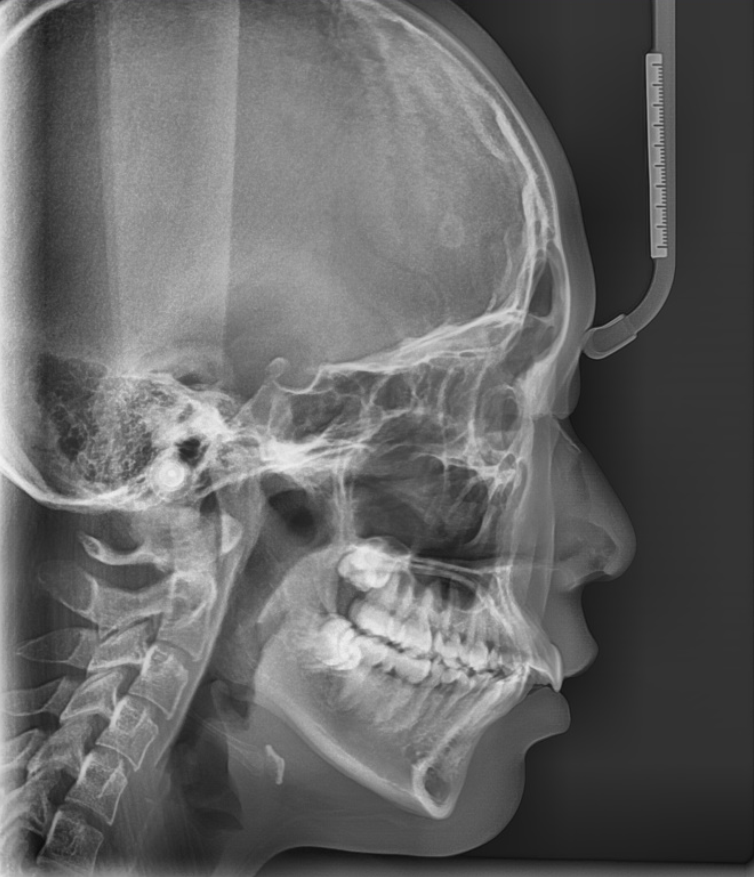

241122 치아를 움직이는데 이렇게 과학적이랍니다~~~